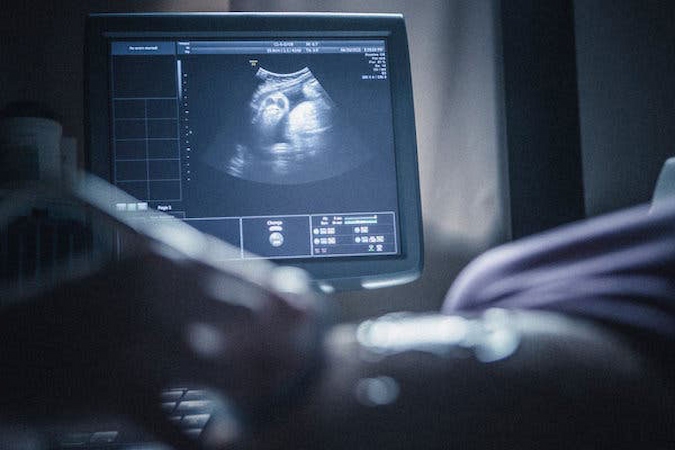

امروزه بررسی سونوگرافی دوره جنینی نوزاد، در ارزیابی وضعیت سلامت جنین جز یکی از مراقبت های دوران بارداری بوده که توسط پزشکان متخصص رادیولوژی انجام می شود.

اینگونه مشکلات مادرزادی باعث ایجاد خطراتی در قلب نوزاد و نیز ایجاد ارتباط غیرعادی بین قسمت های دهلیز راست و دهلیز چپ قلب و در نهایت باعث تغییر شکل دریچه های قلب میشود. اکو کاردیوگرافی قلب جنین، یک روش مناسب برای تشخیص این بیماری ها می باشد. اکو قلب جنین مانند سونوگرافی یک آزمایش تصویری است و توسط پزشک متخصص قلب نوزاد انجام می شود. در این آزمایش برای تولید یک تصویر از قلب جنین از امواج صوتی استفاده می شود.